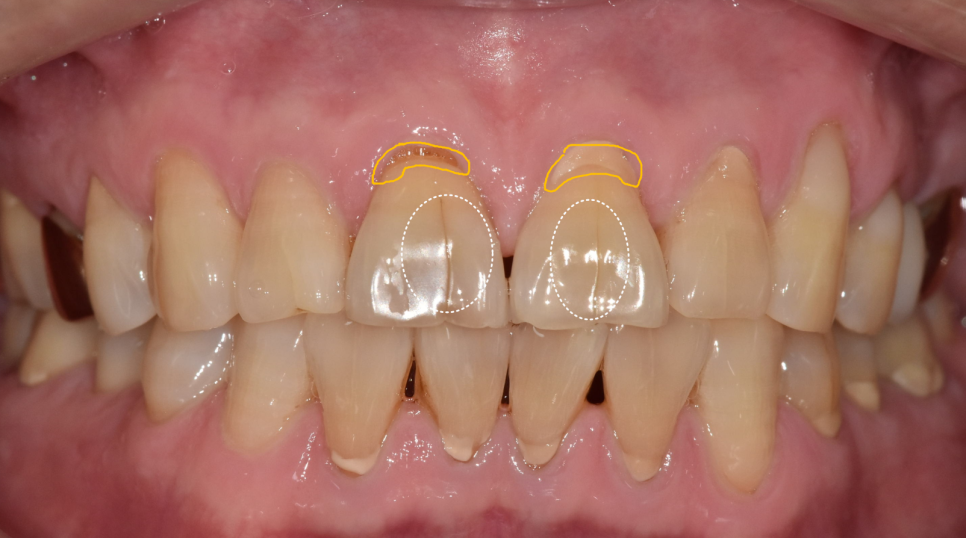

치아를 보는 순간 알 수 있었던 사실 하나는

"아, 이분 딱딱한 음식 좋아하시는구나."였습니다.

위아래 치아의 씹는 면이 전반적으로 다 닳아있었거든요.

특히 문제는 금이 간 앞니였습니다.

240605

보통은 위 앞니가 아래 앞니를 살짝 덮으면서,

가위처럼 음식을 잘라내는 구조를 이룹니다.

하지만 이 분은 위아래 앞니 끝과 끝이

정면으로 맞닿아 있었습니다.

식사할 때마다 마치 못 위에 망치를

계속 내리치듯, 앞니 끝끼리 정면으로 부딪히고 있었던 겁니다.

치아를 살펴보니 앞니 앞면 중앙에 금이 쭉 가 있었습니다.

치경부(치아와 잇몸 경계) 쪽엔 마모가 진행되어 뿌리 쪽이 파여있습니다.

250626 앞니 금 갔을 때, 방치하면 안 되는 진짜 이유 <파절 치료 사례>

특히 금이 더 깊게 간 오른쪽 앞니 통증을 호소하셨습니다.